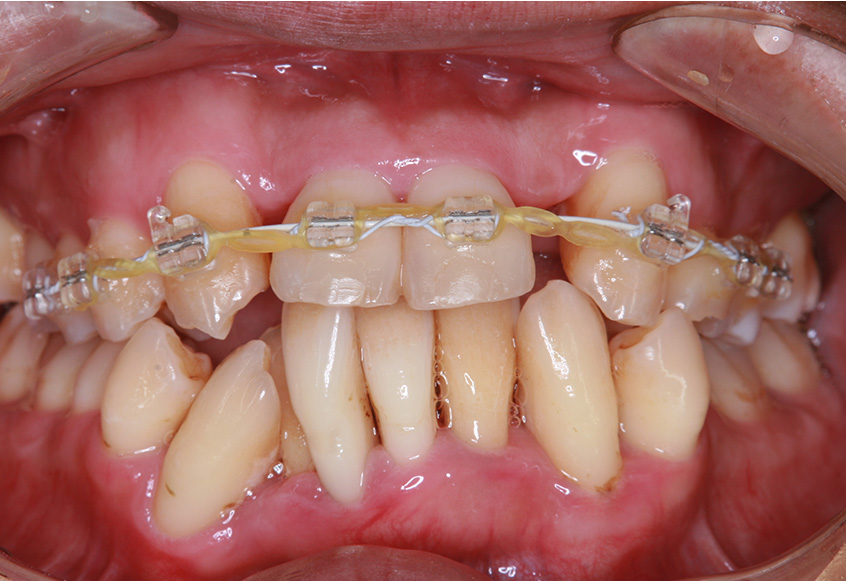

6ヵ月経過すると、矯正治療を終了し、前歯に被せ物の治療を行いました。

最初のお口の中 2025/3/22

被せ物装着

| 治療内容 | 上顎側切歯を2本抜歯した後、上顎の歯にブラケットを装着し、ワイヤー、矯正用ゴムで歯の移動を行いました。その後、被せ物の治療を行って治療を終了しています。 |